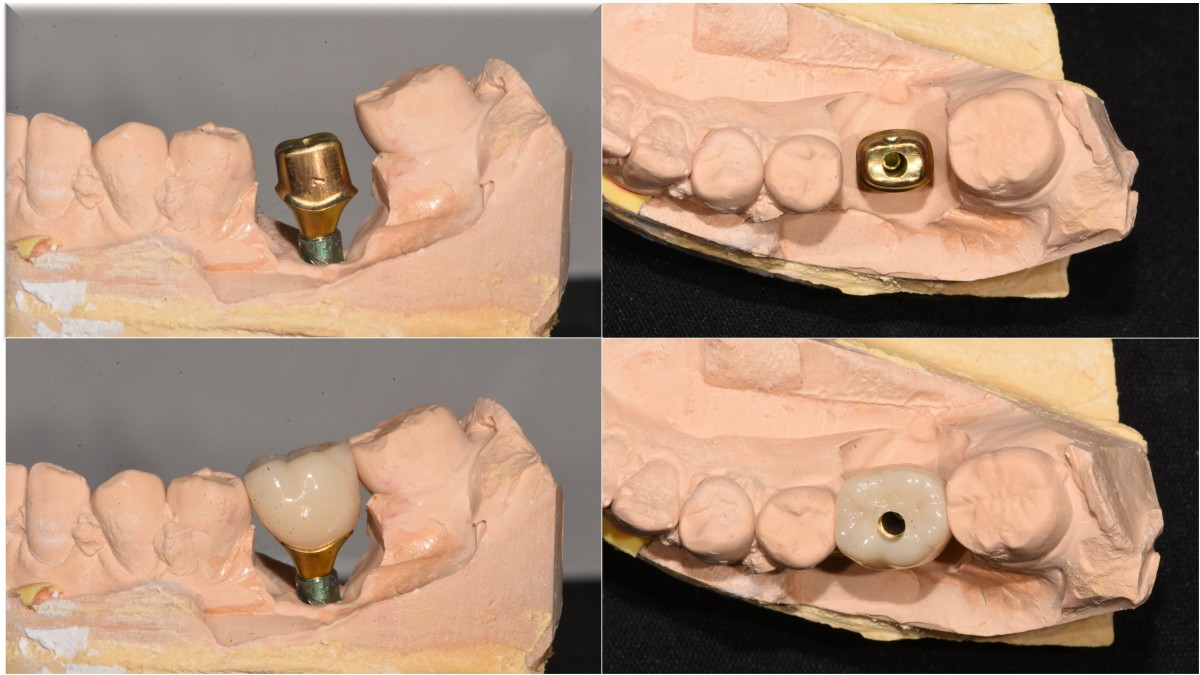

Immediate placement of an implant (Arum Dnetistry NB1, 5*8.5)

Extraction and immediate placement of an implant.

▲Arum Dentistry NB1 fixture (5*8.5mm)